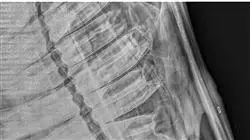

Oggi l'imaging diagnostico è costituito da molteplici modalità e non tutte sono di facile comprensione. Le basi fisiche della risonanza, per esempio, sono un capitolo complesso che non può essere affrontato in modo breve, ma per arrivare a una diagnosi è necessario comprendere le diverse modalità di acquisizione dell'immagine nelle varie tecniche diagnostiche.

Questo Corso universitario affronta in dettaglio le patologie più rilevanti e le modalità di diagnosi più adeguate del sistema muscolo-scheletrico dal punto di vista di un fisioterapista equino. Al termine della formazione, lo studente dovrà riconoscere attraverso le tecniche di diagnostica per immagini le patologie più frequenti nelle alterazioni del sistema muscolo-scheletrico nei cavalli.

In ogni argomento viene descritta la tecnica radiografica della regione anatomica da trattare, rivedendo le proiezioni standard e le proiezioni speciali di ciascuna area da valutare. Successivamente, vengono descritte le variazioni anatomiche individuali che possono essere osservate, nonché i reperti incidentali e la loro interpretazione. Si sviluppano anche le patologie di ogni regione anatomica. Per quanto riguarda l'ecografia, vengono descritte la sua tecnica, le immagini normali e le alterazioni più significative nelle lesioni del sistema muscolo-scheletrico. Infine, vengono analizzate altre tecniche molto attuali come la RM, il TAC, la scintigrafia o il PET.